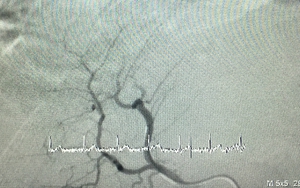

Một bệnh nhân nam bị vỡ khối u gan kèm xuất huyết ổ bụng vừa được các bác sỹ Bệnh viện quận Thủ Đức, Thành phố Hồ Chí Minh, phẫu thuật khẩn cấp và đã thành công.